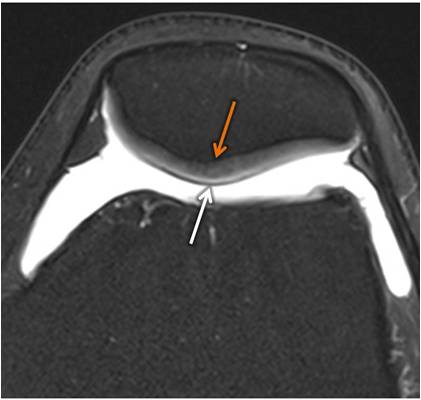

A dor anterior no joelho está frequentemente associada à condropatia, condição relacionada ao desgaste da cartilagem articular.

A osteopatia utiliza técnicas que auxiliam na normalização do eixo biomecânico entre quadril, joelho e tornozelo, contribuindo para a melhora da função articular e redução da dor.